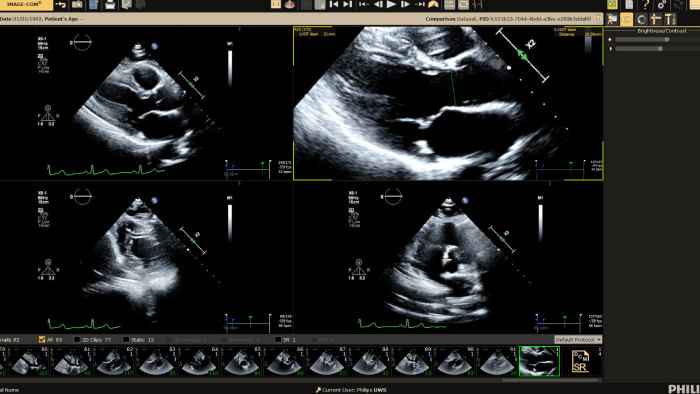

You can still access recordings of 4 full days of hands-on workshops about best practices in multimodality cardiac imaging with expert teams. See first-time-right imaging for cardiac care, including valvular and related diseases, cardiomyopathies, and intracardiac masses and cardiac tumors. Sign up to receive access to these on demand sessions and other news about Philips and cardiac care.

Cardiovascular Ultrasound

Increase diagnosis confidence and clinical efficiency through superior image quality, advanced quantification tool and automation technology.